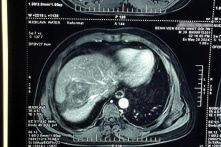

Thường xuyên ăn sống rau muống, rau ngổ, người đàn ông bị sán lá gan lớn ký sinh

Ngay trong thời gian đang điều trị tại bệnh viện, người đàn ông 39 tuổi vẫn thường xuyên ăn cá nướng quấn rau muống, hay thịt vịt quay, hấp ăn kèm rau ngổ sống. Bệnh…